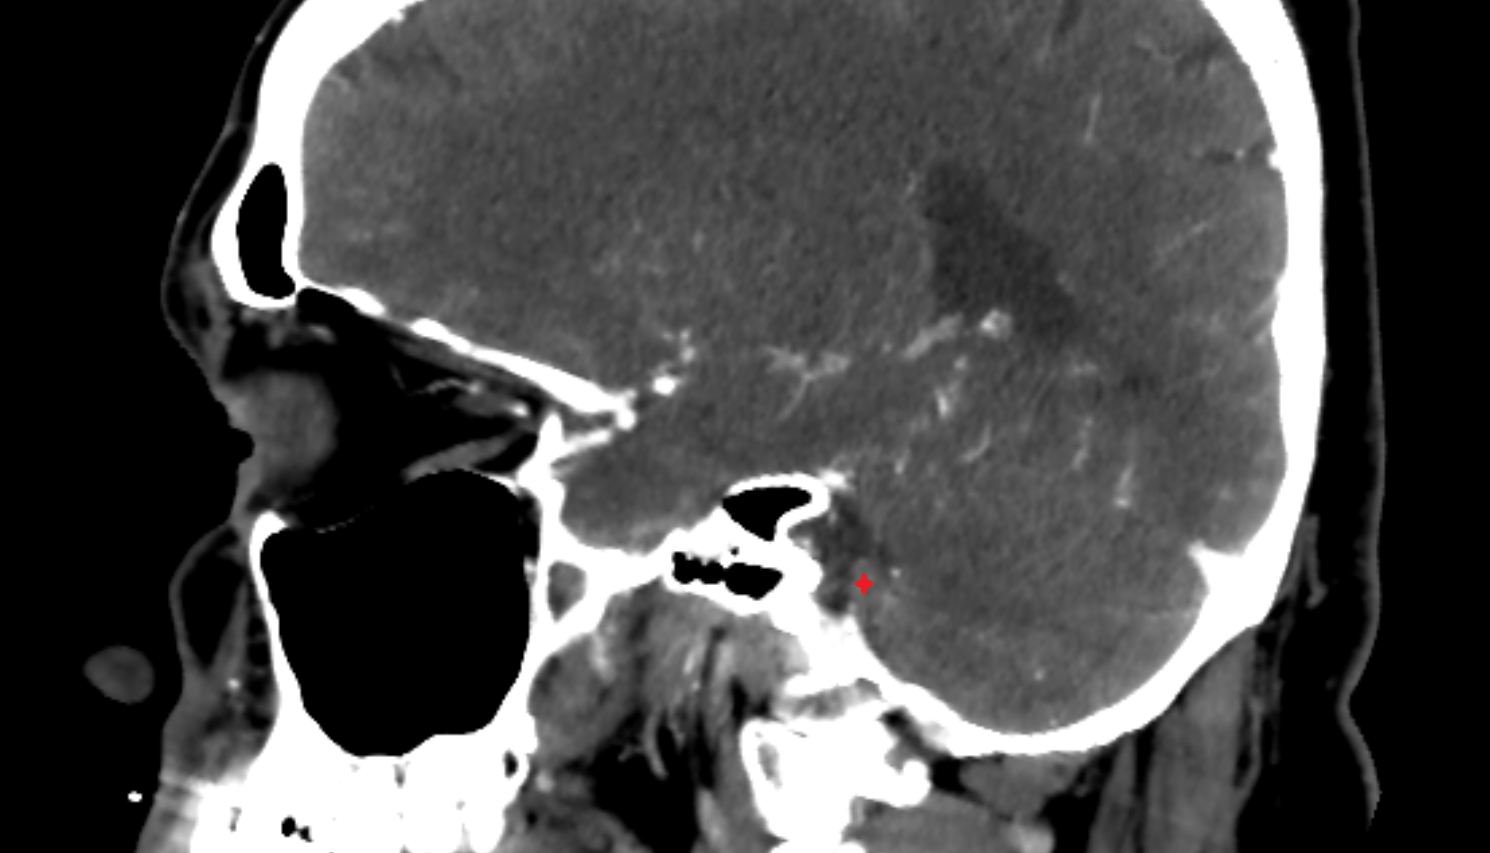

- Temporomandibular joint

- Mandibular condyle

- Mandibular fossa

- Articular disc of temporomandibular joint

- Articular eminence